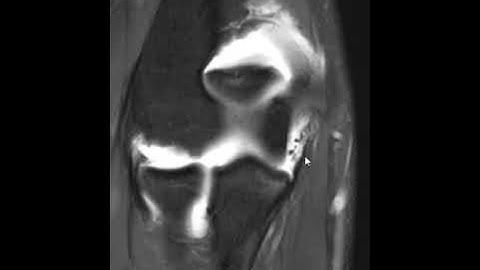

UCL tear from the sublime tubercle